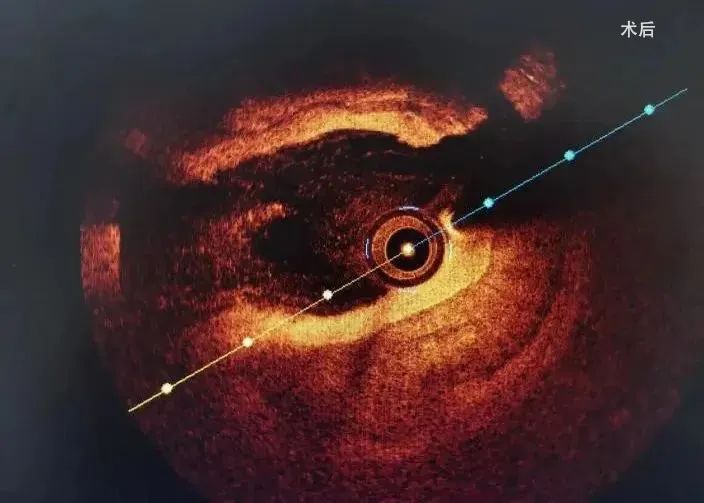

冲击波球囊治疗后,复查OCT提示前降支近、中段原钙化环断裂,钙化病变扩张满意。

冲击波球囊治疗后原钙化环断裂

经过充分的冲击波球囊预处理后,因钙化环得到松解,血管顺应性提升,病变处支架顺利植入。复查OCT及造影提示支架贴壁良好,扩张满意,支架膨胀率达86.24%,无夹层及残余狭窄。

冲击波球囊治疗后,顺利植入支架,无夹层及残余狭窄

OCT检查指示支架膨胀及贴壁良好,膨胀率达86.24%